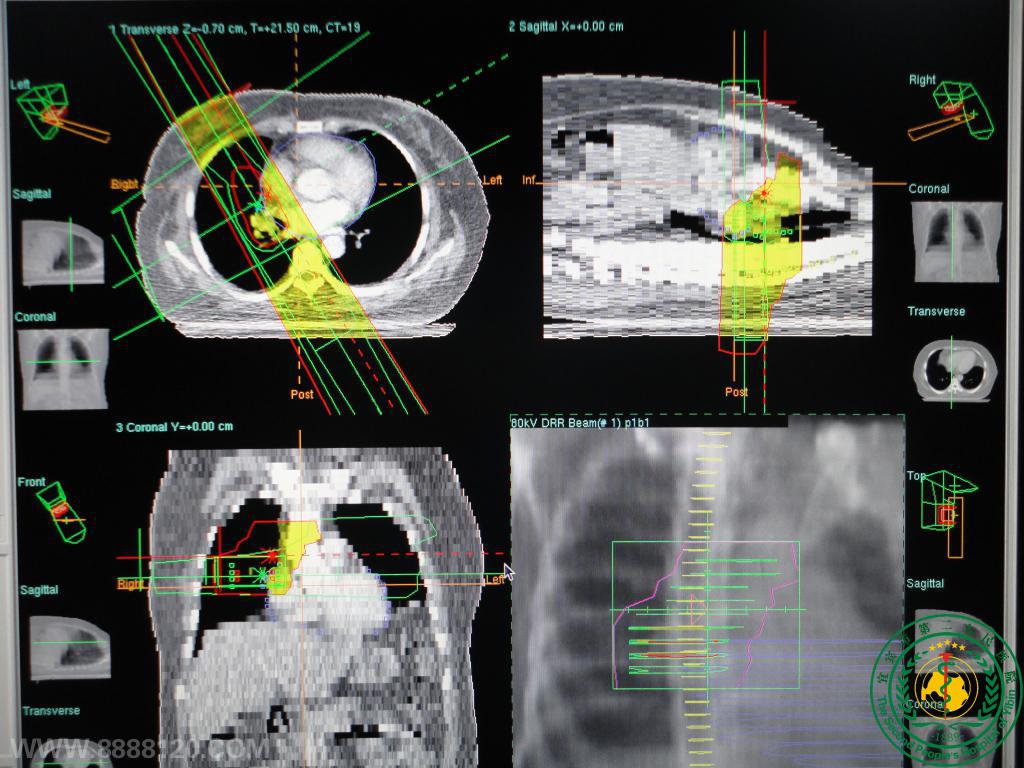

放疗科特色技术

放疗科特色技术3586